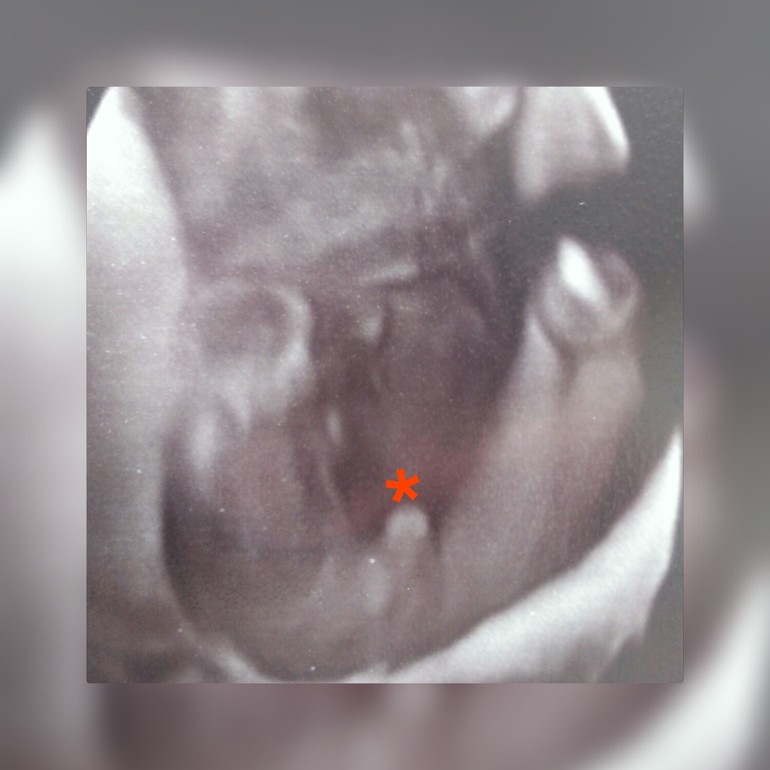

Сходила сегодня на узи)))))

В последнее время очень сильно падает давление((((переживала за ребёночка,врач направила на узи...всё у нашего малышастика хорошо)))) и пол узнали наконец))))))

угадайте кто)))))))))